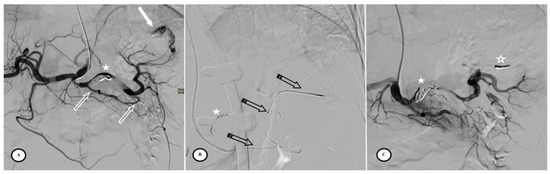

According to the SIR classification, no procedure-related Grade 3 or higher adverse events (AEs) existed. Mild AEs included puncture site hematoma (n = 2/57, 3.5%) and puncture site pain (n = 5/57, 8.7%). Primary efficacy was achieved in 97% of cases but two patients were re-embolized; one for active bleeding on Day 6 (Figure 4) and the other for an arteriovenous fistula on Day 30 (Figure 5). No deaths, rescue splenectomies, or hemorrhagic, infectious, or thromboembolic complications occurred. Secondary efficacy was high, with no cases of necrotic pancreatitis and a high splenic salvage rate (94.7%), as only three cases of < 50% vascularized spleen parenchyma were observed at the consultation on Day 30. The average percentage of vascularized spleens at one month was 86.7% (SD = 14.2%), with more vascularized parenchyma in the AVP group (p < 0.01).

Figure 4.

Secondary pseudoaneurysm formation 6 days after preventive proximal splenic artery embolization (PPSAE). (A) shows PPSAE with a vascular plug (star) and the development of collateral circulation (arrows) alongside pseudoaneurysm formation (curved arrow). (B) displays the dominant collateral circulation via the gastroepiploic artery (striped arrows). (C) Microcatheter selection of the gastroepiploic artery for distal embolization (blank arrows).